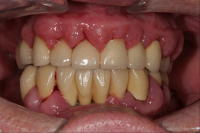

En bakteriellt orsakad inflammation som leder till en progressiv förlust av tändernas stödjevävnader.

Diagnostik

Det viktigaste måttet att påvisa sjukdom i parodontala vävnader är blödning.

- Gingivit blödning vid sondering, ingen benförlust, fickdjup 3 mm eller mindre. Parodontitis superficialis: fickdjup 5 mm eller mindre, horisontell och/eller angulär benförlust mer än 2 mm och blödning/pus vid sondering.

- Parodontitis profundus fickdjup 6 mm eller mer, horisontell och/eller angulär benförlust mer än 2 mm och blödning/pus vid sondering.